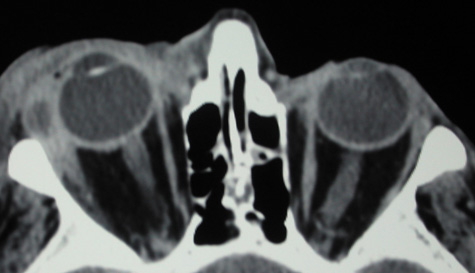

With preseptal inflammation, CT demonstrates soft tissue swelling of the eyelids and tissue adjacent to the orbital septum (Fig. 15). The orbit is not involved, and usually the sinuses do not show evidence of inflammation. The distinction between inflammatory preseptal cellulitis and edema cannot be made.63

Fig. 15. Computed tomography showing preseptal cellulitis of left eye. Note that all swelling is anterior to the orbital septum.